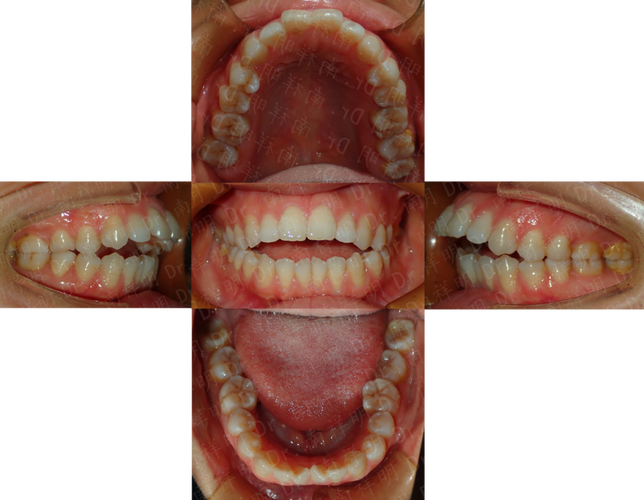

成人正畸的方案设计需兼顾“牙齿排齐”与“面部美学”,北大口腔医院尤为注重个性化方案的定制,医生会通过全面的面部分析、口内检查、功能评估及影像学检查,结合患者的职业、年龄、美观需求及治疗预期,制定差异化的矫治策略,对于前牙深覆合、深覆盖且伴有面部凹陷的患者,可能需要通过正畸-正颌联合治疗改善咬合关系与面部轮廓;对于轻度牙列拥挤且对美观要求极高的患者,隐形矫治或舌侧矫治则成为首选,既能实现牙齿移动,又能最大限度满足美观需求,在方案沟通阶段,医生会利用3D动态模拟技术,向患者直观展示牙齿移动过程及预期效果,让患者充分参与治疗决策,提升治疗依从性。

成人正畸的矫治器选择多样,每种类型均有其适应人群与优缺点,患者可根据自身需求与医生建议选择合适的方式,传统金属托槽矫治器因其强度高、适用范围广、价格相对亲民,仍是复杂病例的首选,尤其是对于需要大幅度牙齿移动、扭转或压低的患者;陶瓷托槽矫治器托槽颜色与牙齿相近,美观性优于金属托槽,适合对美观有一定要求的患者,但需注意避免食用色素较深的食物以防染色;隐形矫治器(如隐适美、时代天使等)凭借其透明、可摘戴、舒适度高、便于清洁的优势,成为近年来成人正畸的热门选择,尤其适合轻度至中度牙列不齐、希望缩短复诊时间的患者,但需患者具备良好的自律性,确保每日佩戴时间不少于20小时;舌侧矫治器将托槽粘贴于牙齿舌侧面,完全隐形,对美观要求极致的患者具有吸引力,但技术难度高、费用昂贵,且初期对发音、口腔舒适度的影响较大,需医生具备丰富的临床经验,以下是常见矫治器类型的对比参考:

成人正畸的治疗流程通常分为以下几个阶段:初诊检查与资料收集、方案设计与沟通、矫治器佩戴与调整、保持器佩戴与维护,初诊阶段,医生会进行全面的口腔检查,包括牙齿排列、咬合关系、牙周状况、颞下颌关节功能等,并拍摄曲面断层片、头颅侧位片、CBCT及面部照片,收集完整数据;方案设计阶段,医生结合检查结果与患者需求,制定详细的矫治计划,并通过3D模拟演示治疗效果,与患者确认后进入矫治阶段;矫治器佩戴后,患者需定期复诊(通常为4-8周一次),医生会检查牙齿移动情况,调整矫治力,确保治疗进度;当牙齿排齐、咬合关系稳定后,拆除矫治器,佩戴保持器以防止复发,保持器通常需全天佩戴6-12个月,之后逐渐减少夜间佩戴时间。